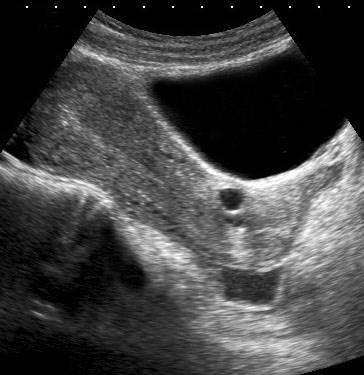

Điều quan trọng là cần hiểu rõ giải phẫu ngoài tử cung.

Một ít dịch trong túi cùng Douglas và một nang Naboth nhỏ (n.) có thể dễ dàng nhận biết, nhưng các cấu trúc được đánh dấu bằng dấu chấm hỏi là gì?

Lưu ý bàng quang căng đầy đang đẩy tử cung ra phía sau.